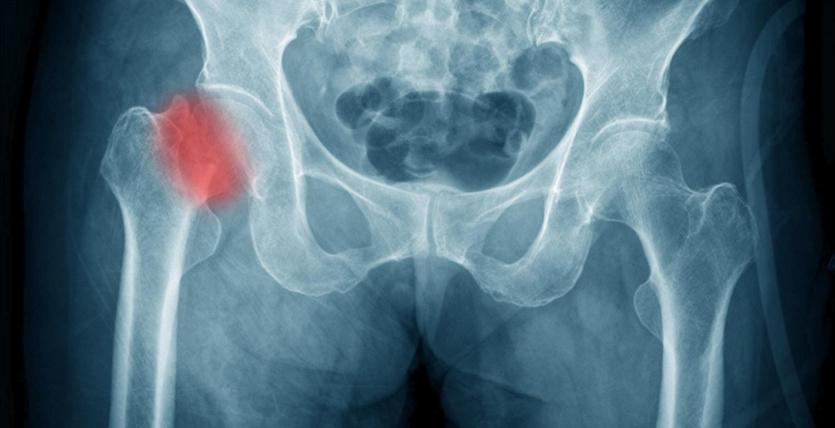

دراسة: النساء النباتيات أكثر عرضة لكسور الورك

وجدت دراسة جديدة أن النساء اللواتي يتبعن نظاما غذائيا نباتيا يرتفع خطر الإصابة لديهن بكسر الورك بنسبة 33% مقارنة بمن يأكلن اللحوم.

ولاحظ الباحثون بعد حوالي 20 عاما ،822 كسرا في الورك بين النساء، حوالي 3%، وأن ارتفاع خطر الإصابة بكسر الورك كان فقط بين النباتيات مقارنة بالنساء اللواتي تناولن اللحوم بانتظام.